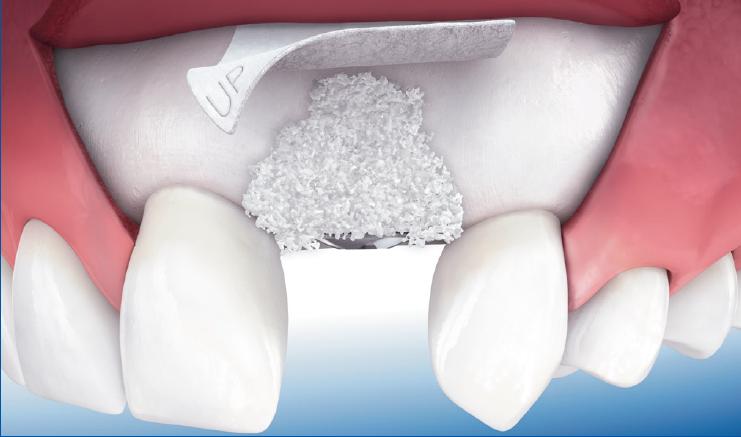

Це хірургічна операція по нарощуванню кісткової тканини в бічних відділах верхньої щелепи, для якісного встановлення імплантатів.

Як одна з методик автокісткової пластики, синус ліфтинг щелепи дозволяє відновити необхідний обсяг кісткової тканини альвеолярного відростка в передбачуваній області фіксації імплантату, за рахунок зменшення простору верхньощелепної (гайморової) пазухи.

Суть цієї операції полягає в формуванні доступу через гребінь альвеолярного відростка в місці передбачуваного встановлення імплантату.

Через утворений отвір в каналі ложа імплантату, проводиться відшарування і підняття мембрани гайморової пазухи (мембрани Шнайдера).

Після підняття мембрани отриманий простір між дном гайморової пазухи і мембраною заповнюється остеотропним матеріалом.

Імплантат впроваджується в це, вже підготовлене ложе після введення матеріалу.

Методика підняття мембрани Шнайдера забезпечує установку і стабільність імплантату, за допомогою збільшення товщини нижньої стінки верхньощелепної пазухи.